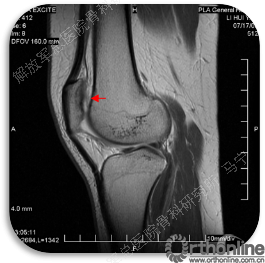

首先经过核磁的检查、评估,初步确定软骨损伤范围,利用T2maping检测序列对软骨的信号区分。图中我们可以看到软骨损伤的范围,并通过计算机计算出大概的面积。

虽然是软骨损伤,但也需要X线评估关节结构,测量双下肢力线,髌骨轨迹,Q角等,排除结构因素引起的软骨损伤,若术前存在发育不良,脱位,半月板损伤,交叉韧带损伤,必须先进行矫形,最后再进行软骨修补,才能达到最佳效果和持久性。